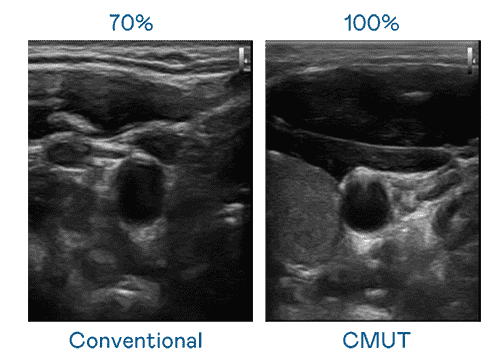

CMUT 技术是一种用电容式微机电元件来产生超音波讯号的技术。。与传统 PZT 压电式技术相比,,,CMUT 频宽增加 30%,,,更宽频的超音波讯号让影像解析度大幅提升,,是实现高影像品质医疗超音波扫描、、促进精准医疗发展的关键技术。。。

大频宽带来超清晰影像

超音波影像的解析度高低,,,首先取决于探头能发出的讯号频宽。。人生就是博 CMUT 可提供高清晰的超音波讯号,,,提供高频宽、、、、高灵敏度、、、影像纹理细节更高的超音波影像,,协助医护人员缩短影像判读时间及利用精准的医疗影像进行诊断。。。。